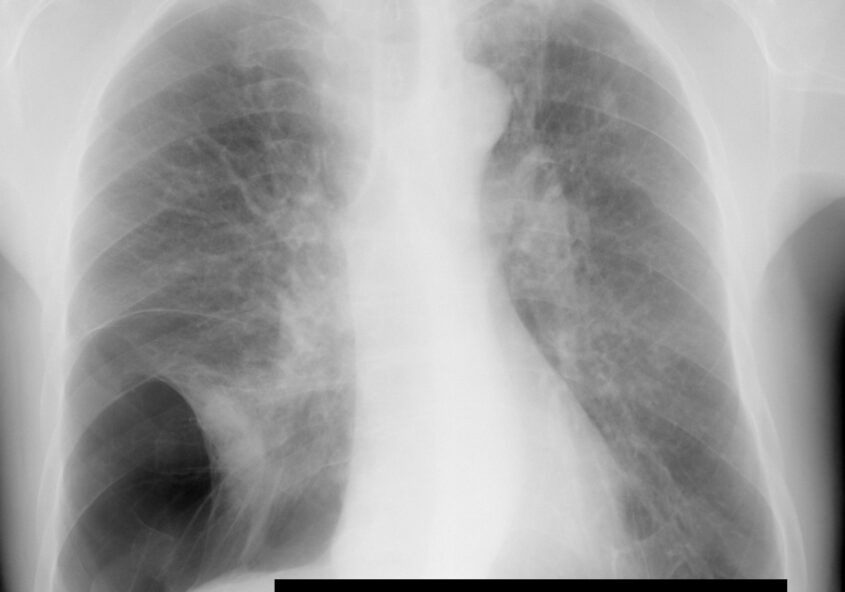

• Ce este emfizemul pulmonar? Răspunsul specialistului

În anul 2001, Iniţiativa Globală pentru Bolile Pulmonare Obstructive Cronice (Global Initiative for Chronic Obstructive Lung Disease, engl.GOLD) a lansat primul său raport, Strategia globală pentru diagnosticul, tratamentul şi profilaxia bronhopneumatiei obstructive cronice (BPOC), bazat pe datele de patogenie existente la acel moment. Într-o perioadă de peste 20 ani multe dintre aceste date s-au schimbat,…